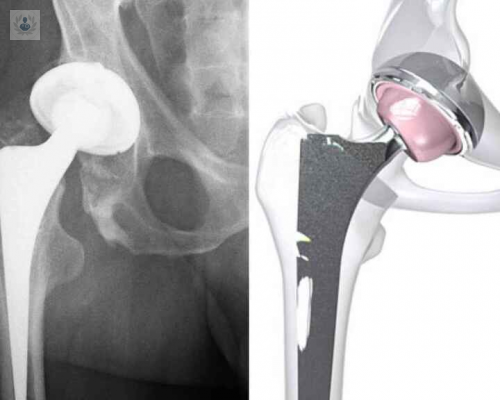

Reemplazo de cadera: conoce todo sobre esta cirugía

La artrosis de cadera es un padecimiento crónico y para el tratamiento de casos muy avanzados se puede indicar el reemplazo de cadera. Se trata de un procedimiento quirúrgico extremadamente reglado y estandarizado, el cual debe ser realizado por un equipo de especialistas para garantizar los mejores resultados. Conozca los detalles sobre esta intervención